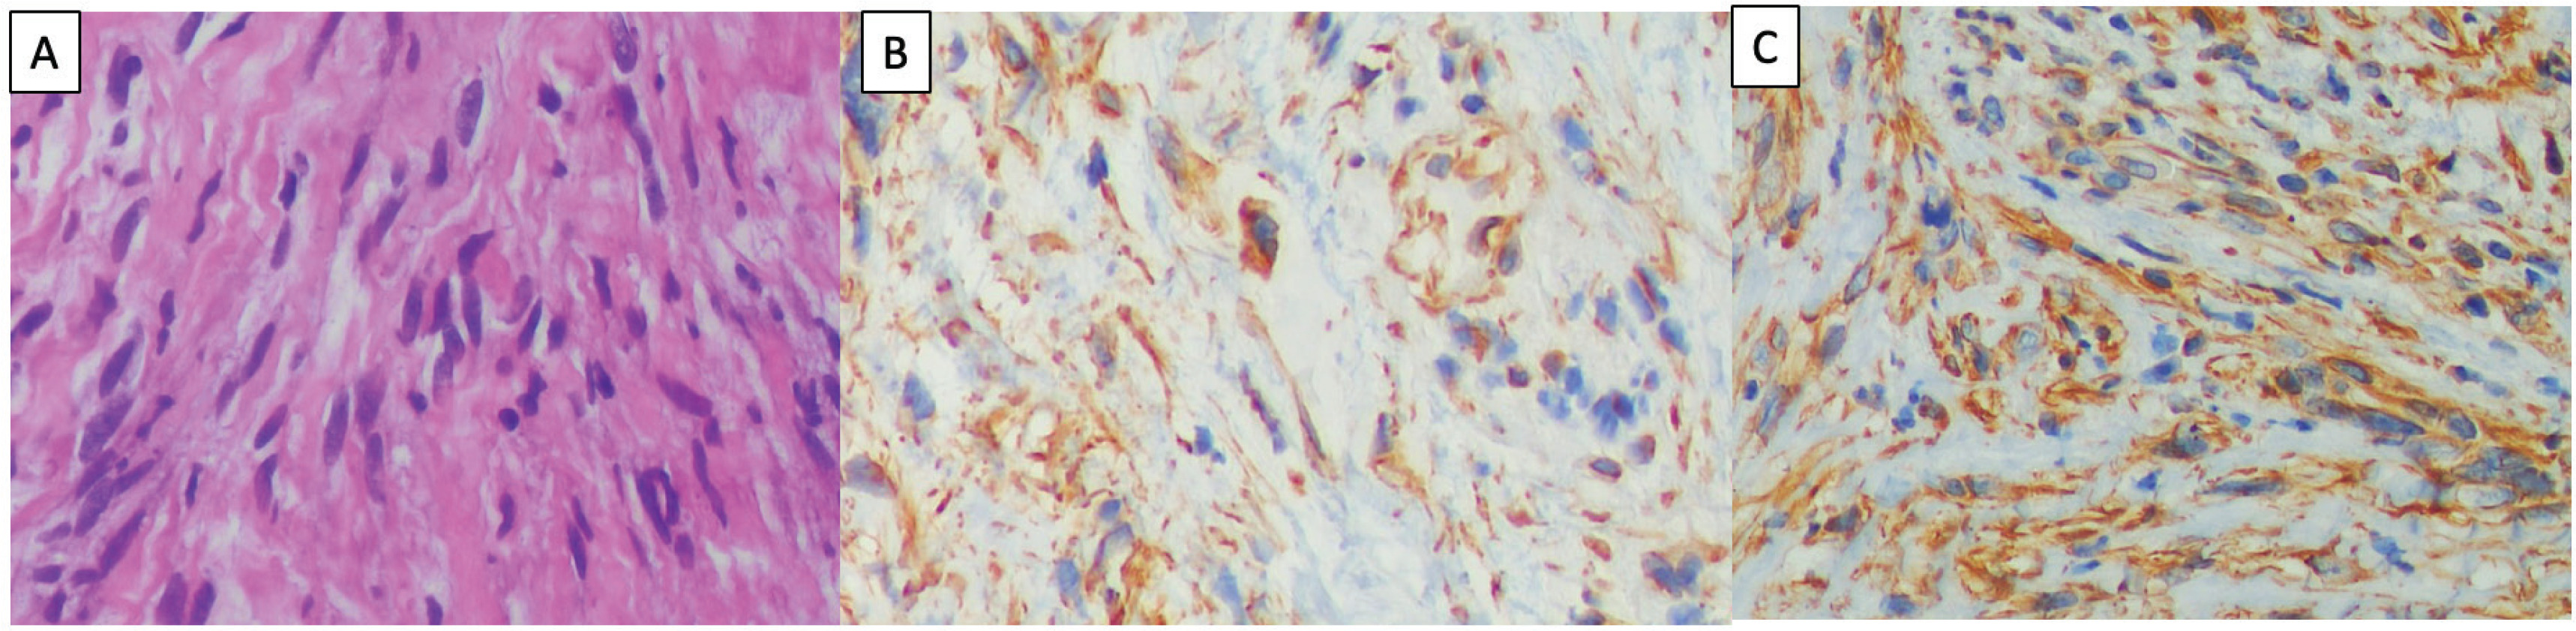

Histopathological examination confirmed a low-grade spindle cell sarcoma, with tumor morphology suggesting a low-grade malignancy of neural differentiation. Immunohistochemical staining showed positive S100 and Ki-67 expression in a small number of cells (Figure 2). There were no epidermal growth factor receptor (EGFR) exon 19 deletions or L858R mutations, and no anaplastic lymphoma kinase (ALK) mutation. Due to health insurance limitations, this case was not tested for MET exon 14 mutations, programmed death ligand 1 (PD-L1), or other molecular examinations beyond EGFR and ALK mutation testing.

Figure 2

Histologic and immunohistochemical features of spindle cell sarcoma: A) Hematoxylin-eosin staining showing cellular haphazardly arranged spindle cell proliferation with prominent stromal hyaline collagen bands (×400); B) Immunohistochemistry showing positive S100 (×400); C) Immunohistochemistry showing positive vimentin (×400)

Spindle cell sarcoma is a rare malignancy that originates from poorly differentiated non-small cell carcinoma and is commonly referred to as sarcomatoid carcinoma5. Pathologically, spindle cell carcinoma is predominantly composed of spindle-shaped epithelial cells that typically lack differentiated carcinoma elements. Sarcomatous lesions are typically large, which leads to a narrowing of the tracheal diameter by more than 50%. In this case, the tumor exhibited low-grade spindle cell morphology, with positive S100 protein staining. The possibility of a malignant tumor with neural differentiation with low-grade histology cannot be ruled out. Additionally, the possibility of higher grade spindle cell tumor involvement in other areas that are not biopsied remains.